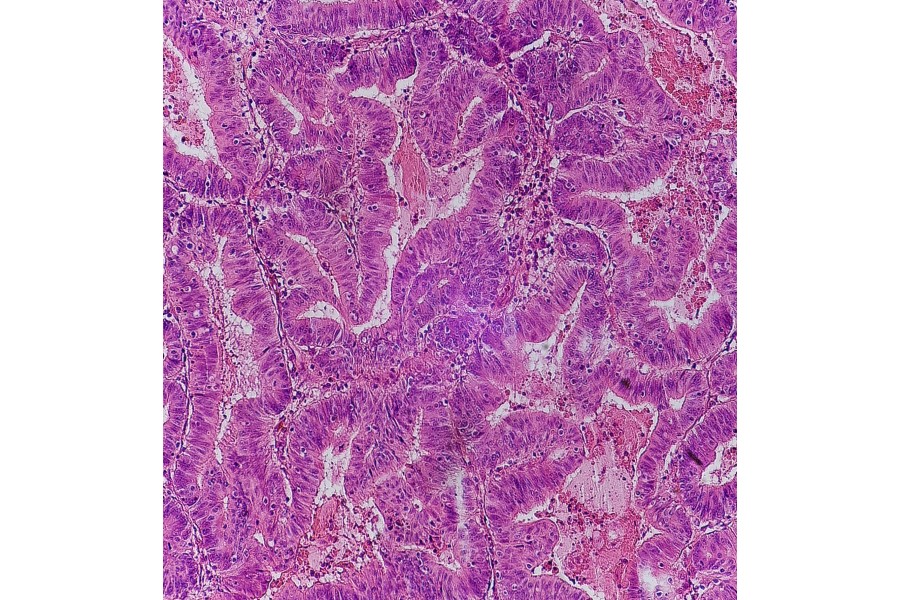

Now, researchers from the University of Southern Denmark and Odense University Hospital have discovered a previously undescribed virus in a common gut bacterium. The virus appears more frequently in patients with colorectal cancer - pictured above is colorectal adenocarcinoma.